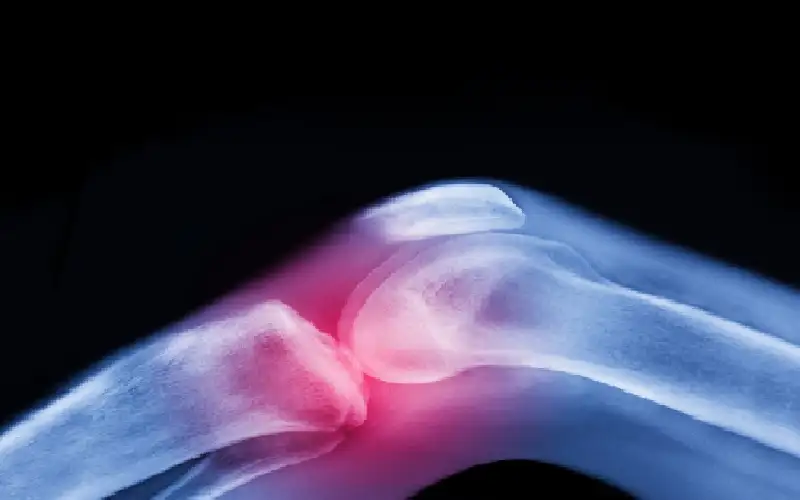

فاتورة الألم.. كيف تحول مرض 'الفيبروميالجيا' إلى عبء بمليارات الدولارات على قطاع الصحة؟